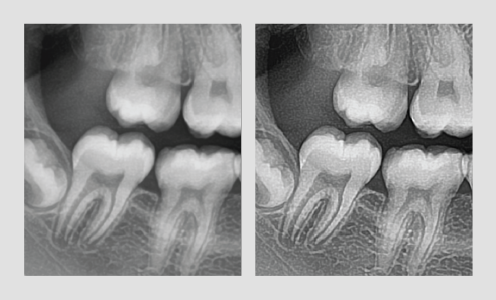

PERMITE UN ANÁLISIS BASADO EN LA INTERPRETACIÓN DEL VOLUMEN

Corre bajo el sistema operativo basado en 3D con base en 2D.

Ahorro de tiempo empleado en el análisis y la comprensión de las imágenes del paciente.

No es necesario ajustar la posición de los ejes, simplemente basta con un clic en representación de volumen 3D y la región de interés se mostrará de inmediato.